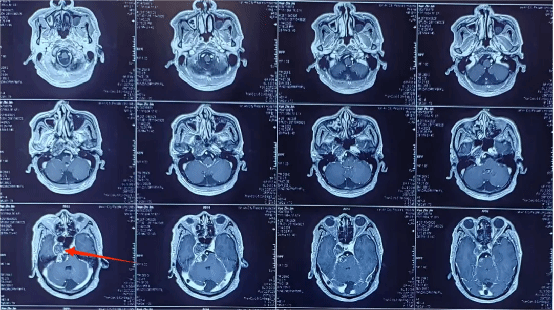

入院后完善了颅脑影像检查,发现右侧桥小脑角区肿瘤已明显挤压脑干。

脑干又称“生命的禁区”,功能受损可能直接影响患者生活质量甚至危及生命安全。经神经外科学科带头人、神经外科二病区主任郭清保详细评估病情,该患者脑干已受压迫,桥小脑角区解剖关系复杂,肿瘤明显挤压脑干及右侧颈内动脉颅内段,同时因患者曾行放疗导致肿瘤与周围组织粘连,分离困难,易出血,手术难度大。